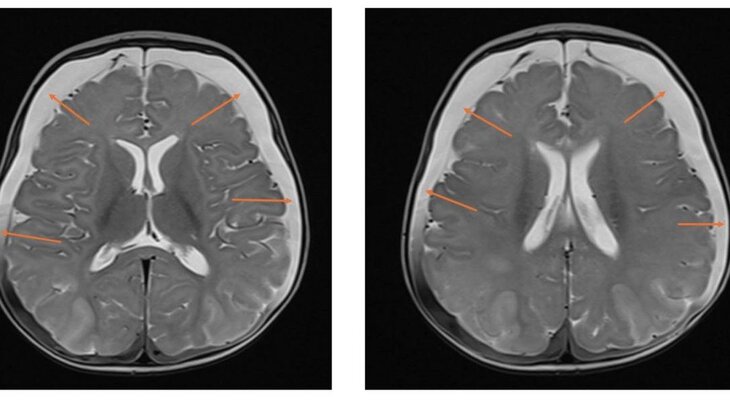

В результате МРТ медики выявили следы перенесенных кровоизлияний и серьезное нарушение кровоснабжения головного мозга. Девочке диагностировали ННН-синдром – редкое генетическое заболевание, при котором организм не способен перерабатывать белок, что приводит к отравлению мозга аммиаком.